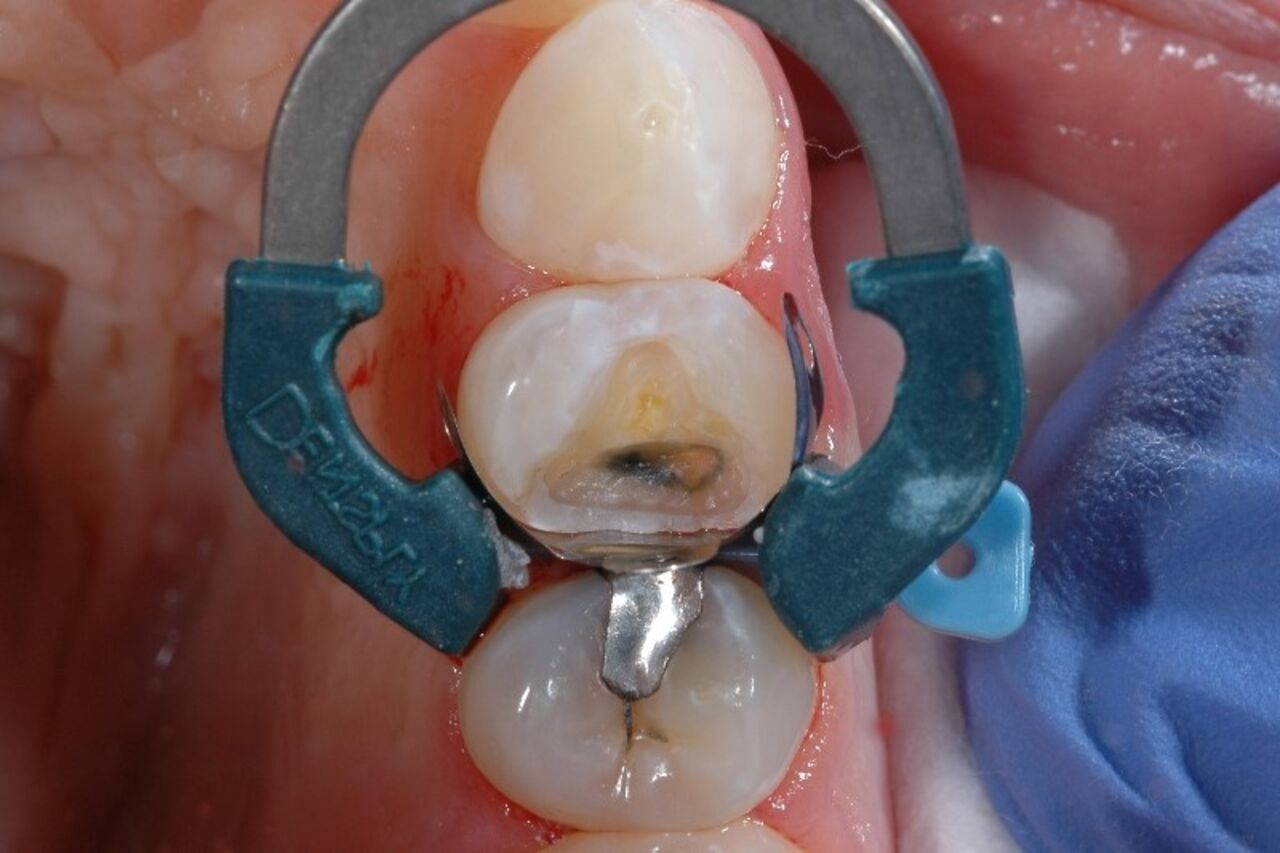

It's not uncommon for a dental practitioner to have a fully booked schedule for the day, when a patient calls complaining of post-operative sensitivity from their recent Class II composite procedure.  After working the patient into the schedule, diagnosing what initially caused the sensitivity can be stressful and challenging given how technique sensitive these procedures are.

What causes post-op sensitivity after composite fillings? Quite a few things, actually - placing composite resins is a complex procedure considering the nature of dentin is close to the pulp, and some studies have estimated sensitivity occurs after 10-15% of posterior composite restorations.1